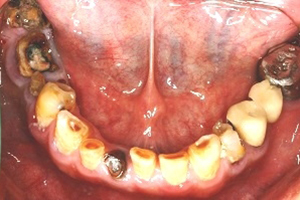

1. 多顆缺牙、牙周病、多顆蛀牙。

治療前-多顆缺牙及牙周病、蛀牙